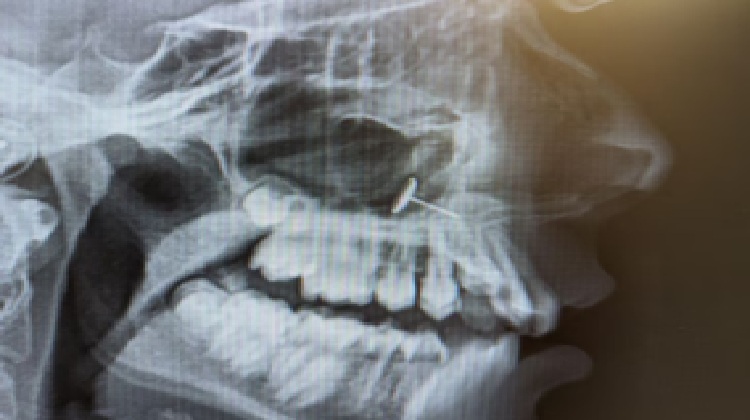

ଓଫେଲିଆ (ଛଦ୍ମ ନାମ) ନାମକ ଜଣେ ମାଆ ତାଙ୍କ ୧୩ ବର୍ଷୀୟା ଝିଅକୁ ଦାନ୍ତରେ ବ୍ରେସେସ୍ ଲଗାଇବା ପାଇଁ ଓର୍ଥୋଡଣ୍ଟିଷ୍ଟଙ୍କ ପାଖକୁ ନେଇଥିଲେ। ସେ କେବେ ଭାବି ନଥିଲେ ଯେ ଏକ୍ସ-ରେ’ ରିପୋର୍ଟରେ ଏଭଳି କିଛି ଦେଖାଯିବ, ଯାହା ତାଙ୍କୁ ଆଶ୍ଚର୍ଯ୍ୟରେ ପକାଇ ଦେବ। ଡାକ୍ତର ଯେତେବେଳେ ଏକ୍ସ-ରେ’ ସ୍କାନ ଦେଖାଇଲେ, ସମସ୍ତେ ଦେଖିଲେ ଯେ ଝିଅର ସାଇନସରେ ଏକ ଛୋଟ ଧାତବ ଜିନିଷ ଫସି ରହିଛି। ଓଫେଲିଆ ବୁଝି ପାରିଲେ ନାହିଁ ଯେ ଏହା ସେଠାରେ କିପରି ପହଞ୍ଚିଲା, କିନ୍ତୁ ତାଙ୍କ ଝିଅ ତୁରନ୍ତ ବୁଝିଗଲା ଯେ ପ୍ରକୃତରେ କ’ଣ ହୋଇଥିଲା। ଏହି ଘଟଣା ରେଡିଟରେ ପୋଷ୍ଟ ହେବା ପରେ ଭାଇରାଲ ହୋଇଛି।

ଝିଅଟିକୁ ଗମ୍ଭୀର ADHD (ଅଟେନସନ ଡେଫିସିଟ ହାଇପରଆକ୍ଟିଭିଟି ଡିସଅର୍ଡର) ଥିଲା ଏବଂ ସେତେବେଳେ ତା’ର ଆତ୍ମ-ନିୟନ୍ତ୍ରଣ ପ୍ରାୟ ଶୂନ୍ୟ ଥିଲା। ସେ ତା’ର କାନ ଛିଦ୍ର ପାଇଁ ବ୍ୟବହୃତ କାନବାଲି ନେଇ ନାକ ଛିଦ୍ର କରିବାକୁ ଚେଷ୍ଟା କରିଥିଲା। ପ୍ରଥମେ ସେ ବାହାରୁ ଚାପ ଦେଇଥିଲା, କିନ୍ତୁ ପରେ ଭିତରୁ ଠେଲିବାକୁ ଚେଷ୍ଟା କରିଥିଲା। ଏହି ସମୟରେ ବୋଧହୁଏ ଛିଙ୍କ ଆସିଥିଲା କିମ୍ବା ଭୁଲ ଦିଗରେ ଠେଲା ଯାଇଥିଲା, ଯାହାଫଳରେ ପିୟରସିଂ ତା’ର ନିଶ୍ୱାସ ସହ ଭିତରକୁ ଯାଇ ସାଇନସରେ ଫସିଗଲା। ଝିଅଟି ଏ ବିଷୟରେ ତା’ର ମାଆଙ୍କୁ କିଛି କହିନଥିଲା। ତାକୁ ଲାଗିଥିଲା ଯେ ଏହା ବୋଧହୁଏ ଗଳା ଦେଇ ତଳକୁ ଚାଲିଗଲା, କାରଣ ତାକୁ କୌଣସି ଯନ୍ତ୍ରଣା କିମ୍ବା ଅସୁବିଧା ଅନୁଭବ ହୋଇନଥିଲା। ଧୀରେ ଧୀରେ ସେ ଏହି ଘଟଣାକୁ ମଧ୍ୟ ଭୁଲିଗଲା। ବ୍ରେସେସ୍ ପାଇଁ କରାଯାଇଥିବା ଏକ୍ସ-ରେ’ରେ ଏହି ରହସ୍ୟ ଖୁଲିଥିଲା। ଏହି ଏକ୍ସ-ରେ’ ରିପୋର୍ଟ ସୋସିଆଲ ମିଡିଆରେ ସେୟାର ହେବା ପରେ ଏହା ତୁରନ୍ତ ଭାଇରାଲ ହୋଇଛି ଏବଂ ୭୩ ହଜାରରୁ ଅଧିକ ଆପଭୋଟ ମିଳିଛି।